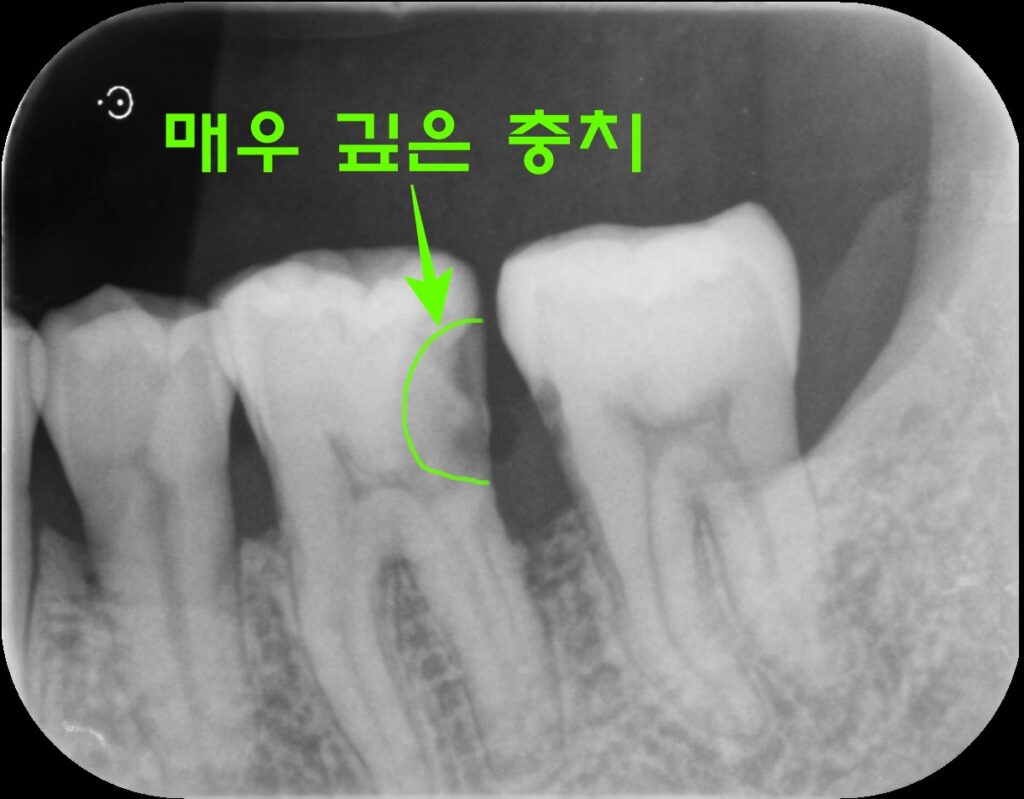

X-ray와 임상 검사 결과, 우식의 깊이가 실제로 상당했습니다. 신경(치수)에 근접하거나 이미 영향을 미쳤을 가능성이 높은 상태로, 치아를 살리는 것이 쉽지 않아 보였습니다. 그러나 발치 전, 할 수 있는 모든 시도를 해보기로 했습니다.

왜 신경치료가 필요했을까요?

충치가 법랑질과 상아질을 넘어 치수(신경)에 근접하거나 침범했을 경우, 단순 충치 치료만으로는 치아를 유지하기 어렵습니다. 이 경우 근관치료(신경치료)를 통해 감염된 신경 조직을 제거하고 내부를 깨끗이 소독·충전해야 합니다.

이번 증례는 어금니의 해부학적 구조상 근관이 복잡하게 분지되어 있어 각별히 세심한 처치가 필요했습니다.